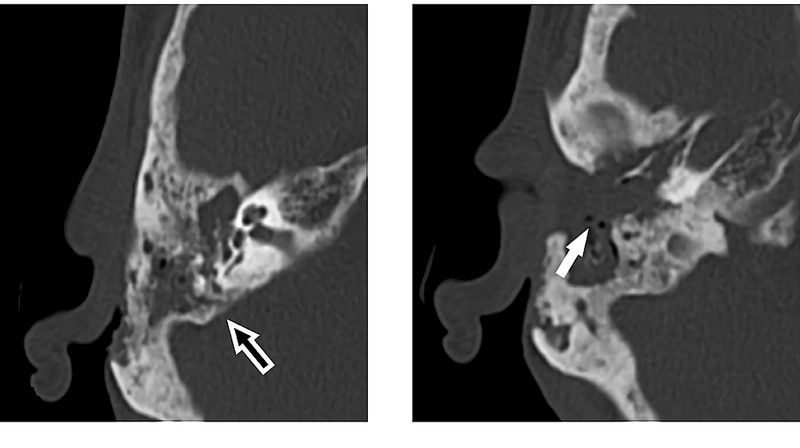

Untuk mencegah komplikasi, pasien langsung menjalani operasi dengan pengangkatan (reseksi) larva, sekuester tulang nekrotik, dan mukosa yang terkena. Pascaoperasi, pasien mendapat amoksisilin–klavulanat untuk mencegah infeksi sekunder serta terapi lokal berupa suspensi oksitetrasiklin dan hidrokortison. Pada kontrol empat bulan pascaoperasi, tidak ditemukan kekambuhan. (Foto: Journal Cureus).